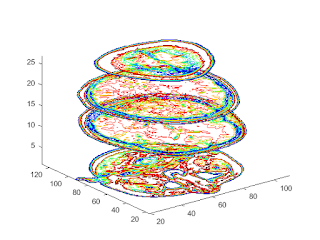

%%3-D Contour Slices figure colormap(twodc) contourslice(D,[],[],[1,12,19,27],10); view(3); axis tight